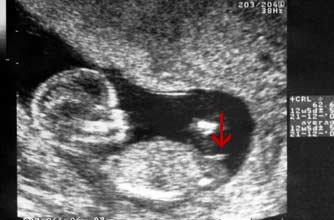

Girl nub: The nub isn't pointing up more than 30 degrees - in fact it's almost horizontal!

小肿块没有指向三十度以上 - 事实上它几乎是水平的!

NT检查大部分的妈妈都是在孕期12周左右做的,这时候宝宝的性征已经发育明显,如果能看到超声的图片,其实是可以看出男女的,我们在图片上可以看到具有性征的一些身体特点,男孩的特征点与身体呈45度角,还多一些,而女孩儿的特征点几乎和躯体平行。还有就是如果是男宝宝,屁股位置会微微上翘,后背脊柱成圆弧状,因为要留空间发育前列腺,相反,女宝宝后背脊柱就相对就平一些。